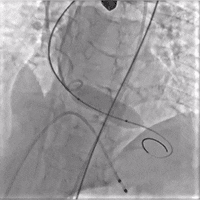

术中影像

左冠术前造影,重度狭窄伴弥漫性钙化

PCI术后左冠造影